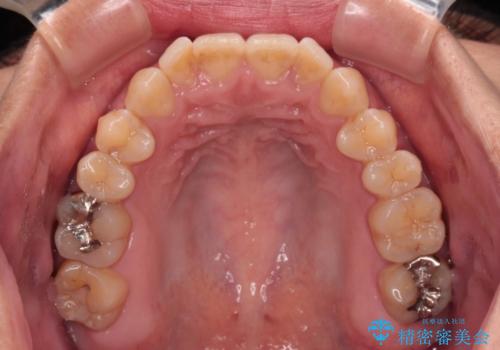

- 極端な開咬を気にして来院された患者様です。

開咬の方の特徴として、幼少期の指しゃぶりの癖や、強い舌の突出癖が挙げられます。

こちらの患者様も強い舌の突出癖が認められたため、矯正治療を行うにあたり、舌のトレーニングをしっかりと行っていただくように指示をいたしました。

開咬はインビザラインが得意とする歯列不正であるため、舌のトレーニングを行いながら、インビザラインにて矯正治療を行うこととしました。

担当医としては、もっと上下の前歯を接触させるところまで治療を進めたいという思いがありますが、今まで咀嚼できなかったものが食べられるようになったということで、この状態で治療終了となりました。